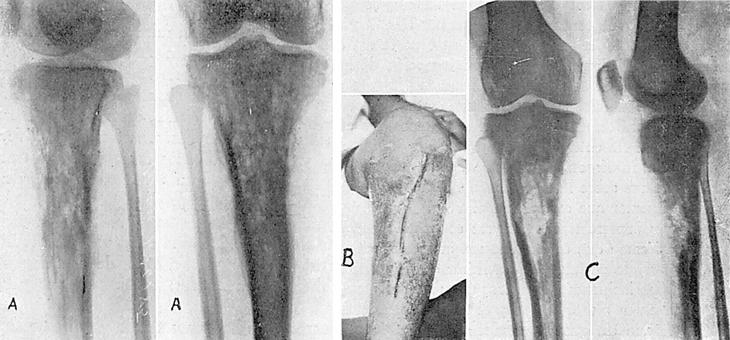

Osteomielitis con gran secuestro (fig. 3A). Operación el 31-X-1946. Secuestrotomía y extirpación de todo el tejido óseo lesionado, previo tratamiento con penicilina. La cavidad resultante después de la intervención es rellenada con un colgajo del gemelo interno.

Figura 3.

Dado de alta con herida completamente cicatrizada el 18-XI-46. Como la tibia ha quedado muy debilitada (fig. 3B), se le recomienda vuelva a los tres meses para reforzar la tibia con injerto óseo.

El 20-IV-47 es reoperado, colocando un injerto de hueso total de tibia derecha. El espacio que queda entre injerto y cresta de tibia se rellenó con pequeños injertos de hueso esponjoso.

Cicatrización por primera intención. Alta el 2-V-47 (fig. 3C).

En 1929 fractura por atropello en tercio inferior de fémur derecho. En 1930 flemón en tercio inferior de muslo derecho, que es abierto. Tratado con vendaje oclusivo. Tarda en cerrar tres meses. Probable osteomielitis. En septiembre de 1946 nuevo flemón en el mismo sitio, que se abre por la cicatriz de la operación anterior y que deja un trayecto fistuloso por el cual se llega al hueso, viéndose en la radiografía la existencia de una cavidad en tercio inferior de fémur (fig. 4A).

Figura 4.

Intervención, previo tratamiento con penicilina, el 16-XI-46. Se encuentra un gran absceso que diseca partes blandas hasta la mitad de tercio medio de muslo. Se practica la extirpación de fungosidades y paredes del absceso, mediante disección laboriosa por estar incluidos en la pared los vasos femorales. Se extirpa la cavidad ósea hasta llegar a hueso sano y se rellena la cavidad resultante con un colgajo de vasto interno. Se continúa con tratamiento con penicilina local e intramuscular.

Cicatrización por primera intención. Alta el 3-XII-46. Radiografía el 2-XI-47 (fig. 4B).

Operada en enero de 1946, sin conseguir curación de la osteomielitis, quedando en octubre del mismo año cicatriz adherente a huesos en tercio superior de tibia en su cresta y cara medial con trayectos fistulosos que llegan a hueso. Análisis bacteriológico. Estafilococos dorados, algunos piociánicos. Radiografía (fig. 5A).

Figura 5.

Intervención el día 30-X-46, previo tratamiento con penicilina. Se encuentra una lesión en metáfisis superior de tibia, teniendo que practicar una extirpación del tejido óseo que deja una cavidad del tamaño de una ciruela. Por debajo de ella, el hueso tiene un aspecto ebúrneo, que no es extirpado. Extirpación de toda la piel cicatrizal hasta llegar a piel sana. Como no es posible rellenar la cavidad con un colgajo muscular, se hace un taponamiento con gasa y se cierra la herida, dejando dos drenajes de vidrio para poder practicar el cierre de la herida operatoria. Hay que tallar un colgajo de pedículo inferior en cara externa de pierna. Se continúa el tratamiento con penicilina.

El 4-XI-46 se practica nueva intervención. Se extraen las gasas y se rellena la cavidad con injertos procedentes de espina ilíaca. La herida operatoria cicatriza por primera intención, excepto en su tercio inferior, en donde queda un orificio que da salida a una serosidad purulenta.

El 14-XII-46 en vista de que sigue segregando una serosidad purulenta por la pequeña fístula, en el tercio inferior de la herida se abre nuevamente y se extirpa la zona ebúrnea, rellenado el espacio con un colgajo de tibial anterior, para mantener el cual en su sitio es necesario practicar unos taladros en tibia. Cicatrización por primera intención.

En 14-IV-47 (radiografía el 10-I-47, fig 5B), y a consecuencia de una caída, sufre esta enferma una fractura de la tibia operada por debajo del sitio de la intervención, que consolida normalmente.